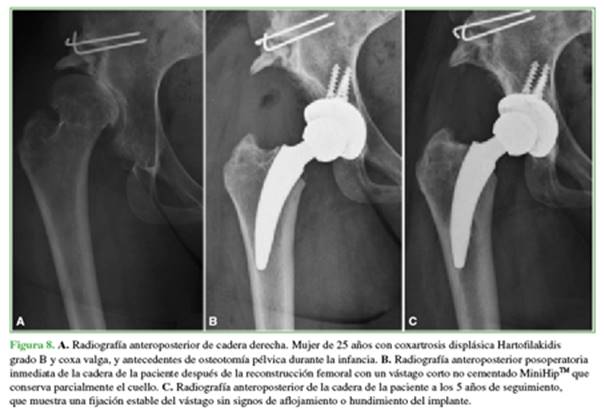

Con el objetivo de analizar los problemas técnicos encontrados al reconstruir el fémur proximal de pacientes con artrosis secundaria a displasia congénita de cadera tratados con una ATC utilizando un vástago corto, se analizó prospectivamente una serie consecutiva de 116 casos con diagnóstico de displasia de cadera tratados con tallo de conservación cervicometafisaria tipo 2B.42

La población de pacientes consistió en 11 mujeres y 6 hombres con una edad promedio de 43 años (DE ± 9.97). En cinco casos, la displasia de cadera fue bilateral; en uno caso, se realizó ATC bilateral en un tiempo y, en cuatro de estas caderas, se realizó un tratamiento quirúrgico secuencial en diferentes etapas debido a las posibles complicaciones de cirugías bilaterales complejas en un tiempo que requieren reconstrucciones sustanciales. El IMC promedio fue de 27 kg/m2 (DE ± 4,50). Cuatro casos presentaron antecedente de osteotomía pélvica durante la infancia (2 osteotomías de Salter y 2 de Chiari), mientras que cuatro casos habían sido sometidos a una osteotomía desrotadora y una osteotomía varizante de cuello femoral. El seguimiento medio fue de 41.22 meses (rango 24-61).

Resultados

Todos los pacientes mostraron una mejoría estadísticamente significativa cuando se compararon los valores preoperatorios y posoperatorios del HHSm (54,19 vs. 94,57; p = 0,0001) y de escala analógica visual de dolor (8,71 vs. 0,71; p = 0,0003). No se encontraron casos de dolor de muslo, inestabilidad o infección. Se diagnosticó un caso de aflojamiento del cotilo y un caso de fractura periprotésica de fémur a los 8 meses y 45 días, respectivamente. La supervivencia global fue del 84,7% a los 5 años (IC95% 64,4-105,3) considerando revisión por cualquier motivo como falla terapéutica. Cuando se evaluó el rendimiento del vástago considerando como falla a la reoperación por aflojamiento del tallo solamente, la tasa de supervivencia fue del 100% a los 5 años (Figura 8).A

B             C